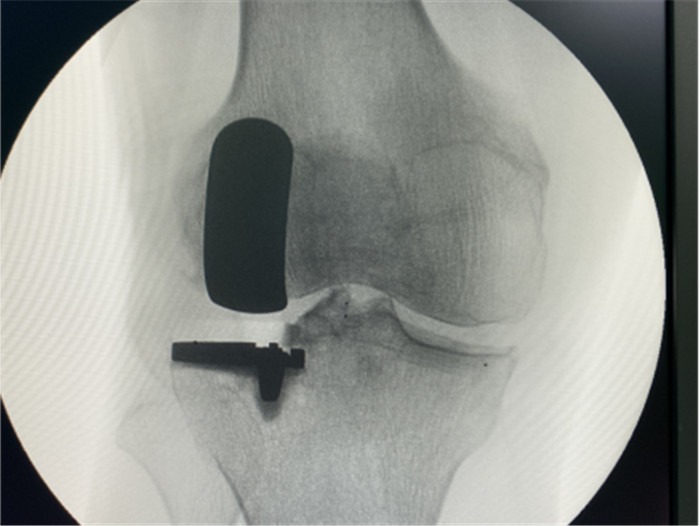

一個單髁置換手術(shù)要想達到理想的手術(shù)治療效果并不簡單,這與假體的大小、方向和松緊度密切相關(guān),其中任何一點出現(xiàn)差池,結(jié)果都會差強人意。為此,羅主任團隊在術(shù)前和術(shù)中進行了精確的設(shè)計和測量,制定周密手術(shù)方案,順利為病人實施手術(shù),幫助膝關(guān)節(jié)“補牙”。

▲右膝關(guān)節(jié)外翻畸形